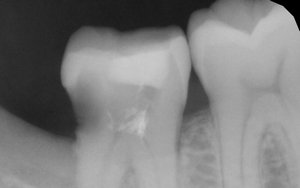

Недавно я обращалась в несколько стоматологий. Мне сказали, что в зубе развивается кариес, и стенки его тонкие. Одни предлагали поставить штифт и новую светоотвердевающую пломбу. Другие говорили, что необходим штифт и коронка.

Естественно, в Вашем случае самый правильный и разумный метод — это протезирование.

Только штифт ставить не нужно. Необходимо восстановить коронковую часть зуба вкладкой, а затем установить коронку. В противном случае, установив штифт и пломбу, Вы рискуете и далее крошить стенки зуба, тем самым потеряете его. Обратитесь к частному стоматологу и протезируйтесь.